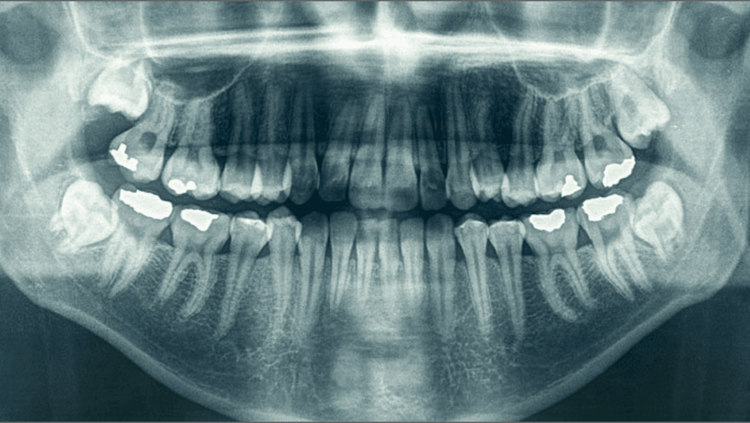

माणूस कितीही सहनशील असला दातदुखी सहन करू शकत नाही. दातदुखीची एक तीव्र सणक जेव्हा डोक्यापर्यंत जाते तेव्हा सगळी कामे सोडून आपण डेंटिस्ट चा रस्ता पकडतो.या लेखामध्ये आपण जाणून घेऊया की का सुरू होते दातदुखी ? दातदुखी कमी करण्याचे आणि ती होऊच नये म्हणून घ्यावयाची काळजी !दातदुखी हा आपल्याला वाटतो पण तो अचानक उद्भवणारा आजार नाही.

आपले दात आपल्याला इशारा देत असतात, आपण तो दुर्लक्ष करून समस्या वाढवून बसतो.